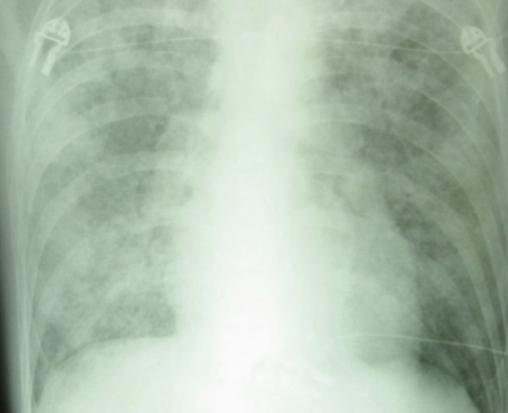

Radiographie de thorax de face. Pneumocystose.